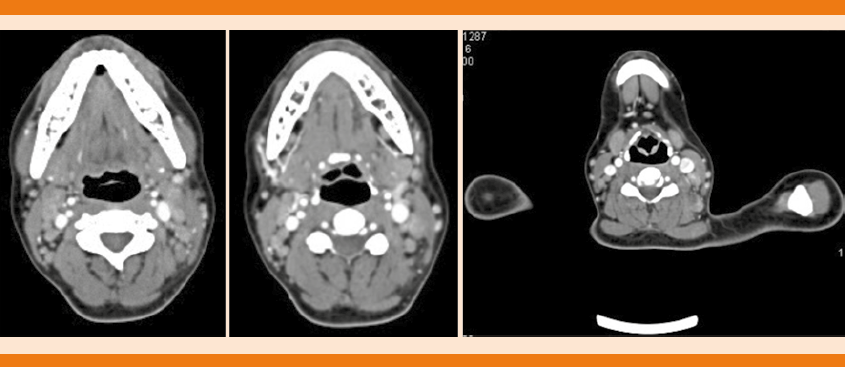

LA TAC de cuello y tórax simple y con contraste IV reportó ganglios de tipo inflamatorio en la región III y supraclavicular izquierdo y ganglios de tipo inflamatorio en la región axilar bilateral (Figuras 1 y 2). Durante su estancia intrahospitalaria tuvo fiebre de 38.3°C que cedió tras la administración de metamizol 1 g, se tomaron muestras de hemocultivo por punción directa que a los siete días de incubación se reportaron negativos.

Figura 1 Tomografía axial computada de cuello con contraste. En la cadena yugular anterior se observan imágenes redondas y ovoides bilaterales que miden entre 2 y 4 mm en su diámetro mayor y en la región supraclavicular izquierda se observa imagen ovoide hipodensa con hilio graso que mide 13 mm en su diámetro mayor.

Figura 2 Tomografía axial computada de tórax con contraste. Los tejidos blandos muestran imágenes ovoides hipodensas con hilio graso en ambas regiones axilares.

Los estudios de imagen (tomografía axial computada, imagen por resonancia magnética, tomografía computada por emisión de positrones) tampoco proveen un diagnóstico concluyente. Los hallazgos que se han relacionado con la enfermedad en tomografía incluyen: linfadenopatía múltiple homogénea que incluye niveles II a V, 94% son menores a 2.5 cm, con infiltración periganglionar y necrosis.15